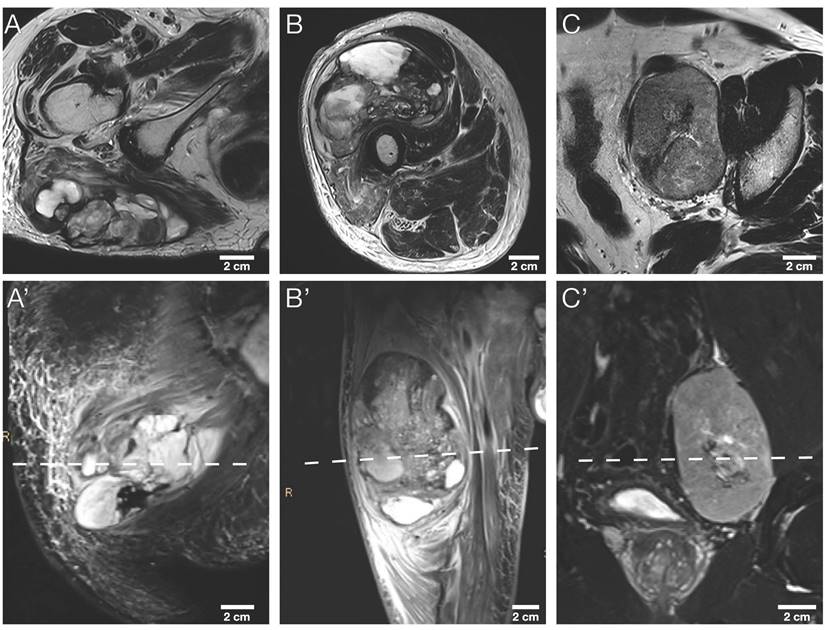

The study sample comprised nine tumor sections, three representative tumor slides from a total of three STS patients: A section of each cranial, middle, and caudal tumor part. More detailed patient characteristics are provided in Table 2. Exemplary axial T2w and coronary T2w-STIR in vivo MR images of the three STS patients are illustrated in Figure 4.

Figure 4

Morphological MRI sequences of the three STS patients. Exemplary axial T2w images (A, B, C) and corresponding coronal T2w-STIR images (A', B', C') of the three STS patients included. The dashed line in the lower row indicates the sectioning plane of axial T2w images in the upper row. STIR, short tau inversion recovery.